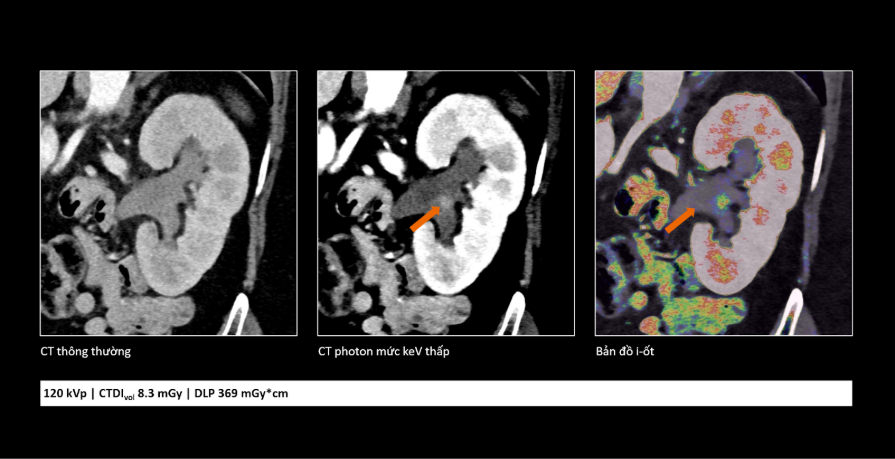

So sánh cho thấy công nghệ cắt lớp vi tính lượng tử không chỉ giúp hình ảnh rõ hơn mà còn cung cấp thêm thông tin, hỗ trợ bác sĩ đánh giá tổn thương chính xác hơn.

Khác với các hệ thống CT truyền thống, công nghệ cắt lớp vi tính lượng tử mang đến một cách tiếp cận mới. Trước đây, CT chủ yếu giúp phát hiện các thay đổi về hình thái như kích thước, hình dạng hoặc cấu trúc của tổn thương. Với công nghệ mới, nhờ khả năng ghi nhận trực tiếp các photon tia X đi qua cơ thể, hệ thống có thể cung cấp thêm nhiều thông tin hơn về đặc điểm của tổn thương trên hình ảnh.

Những thông tin này không chỉ giúp bác sĩ đánh giá hình thái mà còn cung cấp thêm cơ sở để nhận định sâu hơn về bản chất sinh học của tổn thương, từ đó hiểu rõ hơn tình trạng bệnh ở từng người bệnh và đưa ra các quyết định điều trị phù hợp hơn trong xu hướng y học cá thể hóa và y học chính xác hiện nay.

Trong ung thư, việc phát hiện sớm những tổn thương rất nhỏ đóng vai trò quan trọng trong hiệu quả điều trị. Công nghệ cắt lớp vi tính lượng tử cho phép tái tạo hình ảnh với lát cắt rất mỏng (tới 0,2 mm), giúp phát hiện những bất thường mà trước đây có thể bị bỏ sót. Nhờ đó, bác sĩ có thể nhận diện sớm các dấu hiệu bất thường và đánh giá chính xác hơn đặc tính tổn thương, hỗ trợ hiệu quả trong chẩn đoán sớm cũng như theo dõi tái phát.